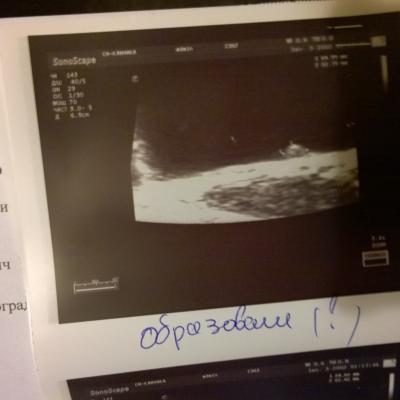

Образование в мочевом пузыре

Здравствуйте. При узи МП нашли образование на нижней стенке, фото прилагаю.

Насколько вероятно, что это доброкачественное? Анализ крови-повышен гемоглобин 161, моноциты 12%. в Моче эритроциты 9-10 в п\з, лейкоциты 2-3 в п\з